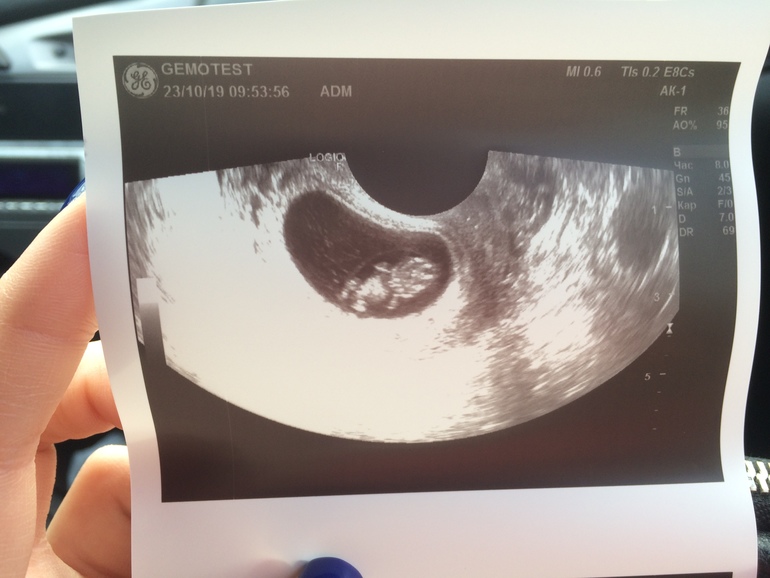

Большой человек )

Всем привет 👋 Хотела поделиться впервые такой чёткой фоткой ) Это мой человек ) УЗИ было 23 октября, почти в 9 недель. Всё хорошо, единственное - две гематомы. Сегодня наконец дошла до гинеколога, встала на учёт. Правда заболел живот после врача, когда сижу - ничего, а когда хожу - ощущение, как на последних сроках: болит живот и хочется родить 🤭 Короче не знаю, впечатлилась ли я своим состоянием, т к мне предложили в больницу или вправду болит.